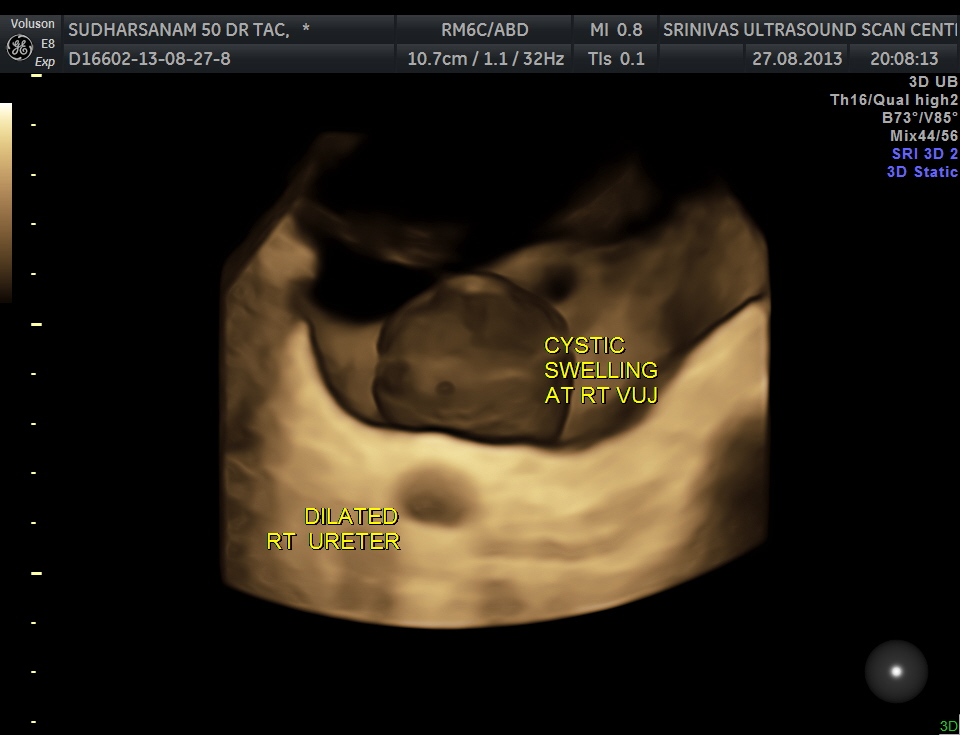

The urinary bladder showed the following :

given below are few other reconstructions

The patient was seen by the urologist and an IVP was done , which proved the diagnosis of orthotopic ureterocele . (a ureterocele entirely within the bladder.)